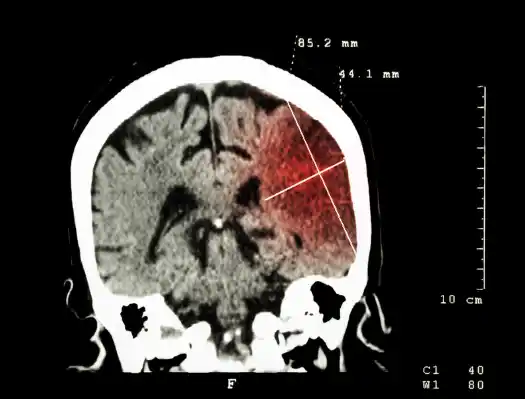

뇌경색 전조증상 및 치료 방법, 좋은 음식에 대해 알아보겠습니다. 뇌경색은 뇌혈관이 막혀서 혈액공급이 제대로 안되면서 발생하는 질환입니다. 뇌경색은 갑작스러운 두통, 신체 마비, 언어장애, 시력장애 등의 증상이 나타날 수 있습니다.

뇌경색이 발생하면 뇌세포가 손상되거나 죽게 되고, 이는 심각한 후유증을 초래할 수 있으므로 발생즉시 응급실로 이송해야 합니다. 그럼 뇌경색 전조증상 및 치료방법, 좋은 음식을 차례대로 알아보겠습니다.

1. 진단 : 뇌경색의 원인을 진단하기 위해 CT, MRI, 혈액 검사 등의 검사를 시행합니다.